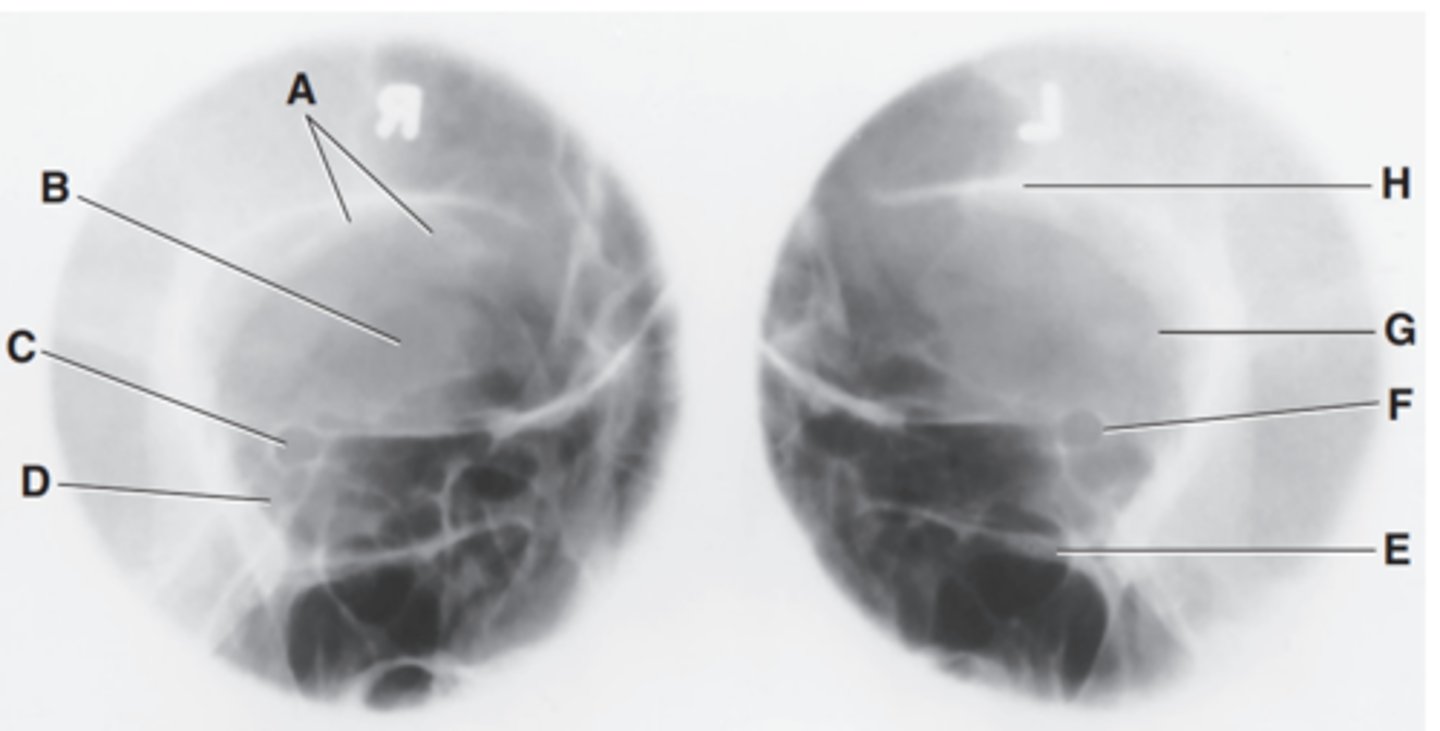

EAM

Label A

Mastoid portion of temporal bone

Label B

Occipital bone

Label C

Lambdoidal suture

Label D

Clivus

Label E

Dorsum sellae

Label F

Posterior clinoid processes

Label G

Anterior clinoid processes

Label H

Vertex of cranium

Label I

Coronal suture

Label J

Frontal bone

Label K

Orbital plates

label L

Cribriform plate

Label M

Sella turcica

Label N

Body of sphenoid (sphenoid sinus)

Label O

Petrous portion of temporal bone

Label P